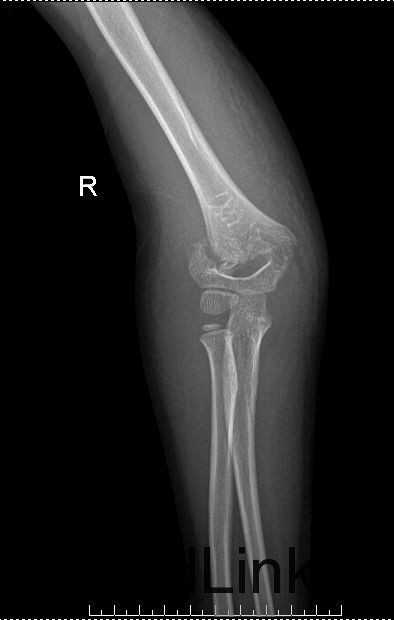

专科检查:步入病房,查体合作。右肘关节肿胀,局部压痛阳性,纵向叩击痛阳性,肘关节功能活动受限明显。肘后三角失常,可触及骨擦音及骨擦感,右上肢皮肤感觉正常,末梢血液循环好。远端手指未见肿胀,各手指感觉、运动良好。 右肘关节正侧位片 :右侧肱骨远端骨质断裂,断端旋转移位。周围软组织肿胀,层次不清。